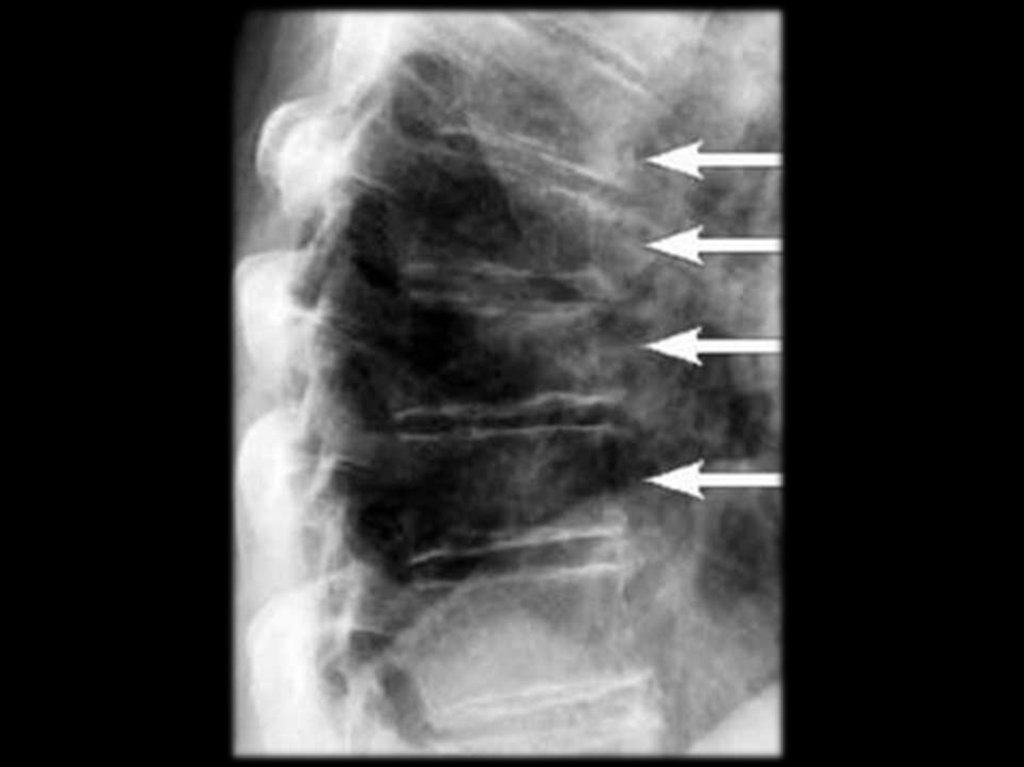

Спинальный стеноз

Сужение просвета спинального канала из-за

выбухания фиброзного кольца в его просвет;

Формирование

остеофитов

в

области

фасеточных суставов;

Врождённый.

Боль возникает при уменьшении диаметра

канала менее 12 мм, при компрессии корешков

“конского хвоста”, при длительной ходьбе.

Характеризуется

следующими

признаками:

двусторонняя,

усиливается

при

нагрузке,

сопровождается парестезиями в голенях. При

выраженном сдавлении развиваются тазовые

расстройства.